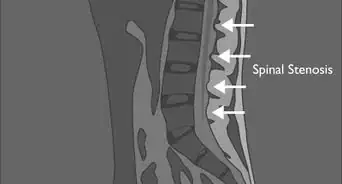

1Visit your doctor. If you have a severely curved back or spine and you find it difficult to stand up straight, consider talking to your doctor. You may have scoliosis or a number of other spinal-related issues.Your doctor may ask you to wear a back brace. Only in the most extreme cases will the doctor recommend spinal surgery. There are many other methods of improving back pain.[17]

3Consult a chiropractor. They'll take a series of x-ray images of your back and spine. Afterwards, they'll be able to measure the exact curvature of your spine to indicate if you have a serious issue. Your chiropractor may also be able to examine your individual vertebrae for malformations, slips, or misalignments. Many of these issues can be treated in office, but if your chiropractor discovers a more serious issue, they'll refer to you a specialist.[21]